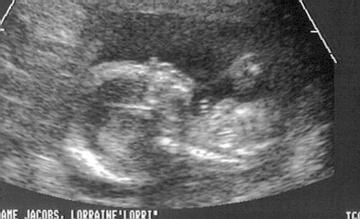

2nd U/S at 17wks4days